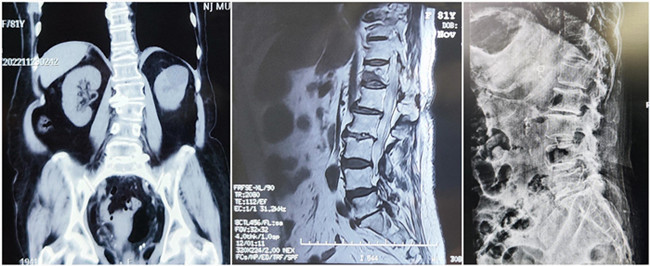

入院診斷:胸椎壓縮性骨折(T12)(主診斷);腰椎滑脫;腦梗死;高血壓1級;糖尿病。

*患者術前影像